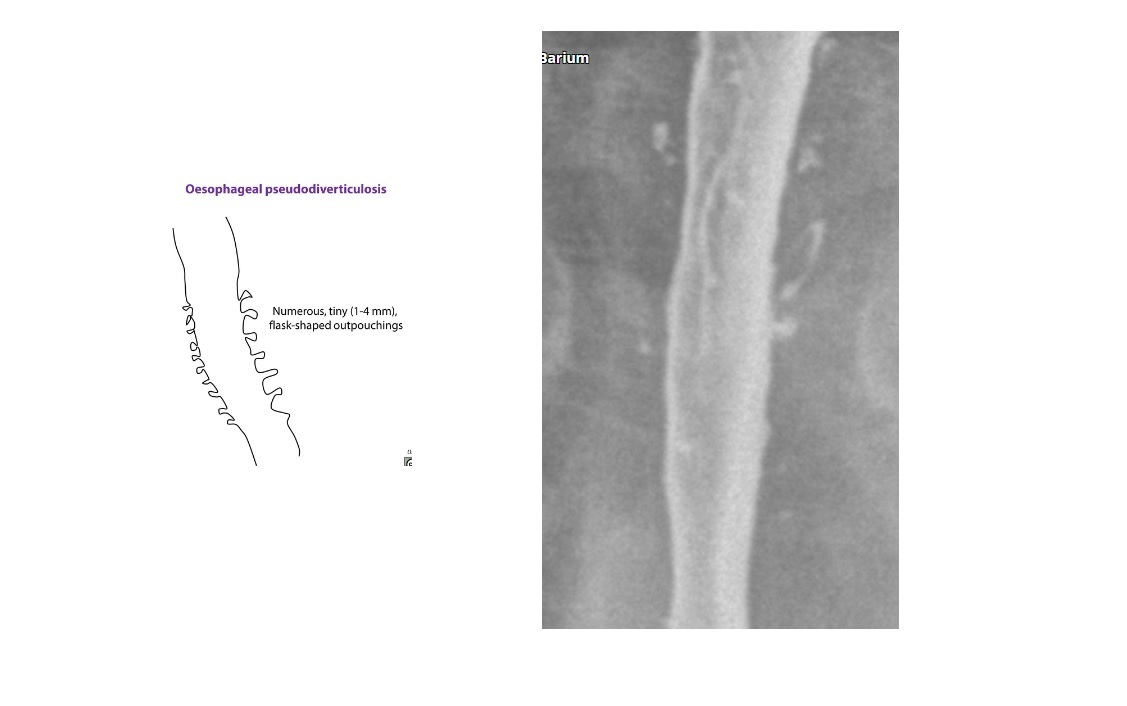

Barium - multiple, tiny (1- to 4-mm depth), flask-like outpouchings in the oesophagus

Oesophageal pseudodiverticulosis

Barium trapped in dilated excretory ducts of submucosal glands

CHRONIC REFLUX* and Candida